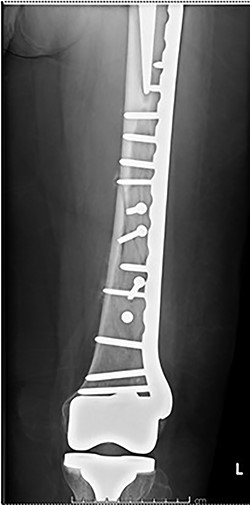

Case 4 (Figs 8–10): once again, screw placement too close to the fracture site has resulted in internal plate stresses exceeding its load-bearing capacity.

Inter-fragmentary screws have been utilized here. This lady may have benefited from placing an anterior bridging plate at the time of her original procedure if it was not possible to avoid this screw configuration.